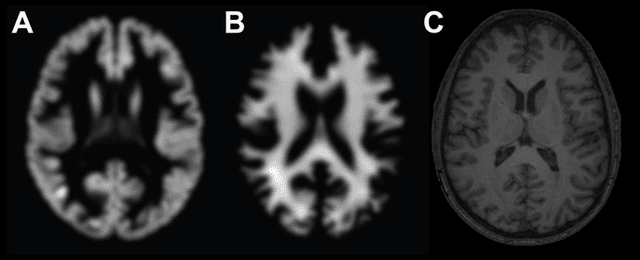

Abstract:Machine learning analysis of neuroimaging data can accurately predict chronological age in healthy people and deviations from healthy brain ageing have been associated with cognitive impairment and disease. Here we sought to further establish the credentials of "brain-predicted age" as a biomarker of individual differences in the brain ageing process, using a predictive modelling approach based on deep learning, and specifically convolutional neural networks (CNN), and applied to both pre-processed and raw T1-weighted MRI data. Firstly, we aimed to demonstrate the accuracy of CNN brain-predicted age using a large dataset of healthy adults (N = 2001). Next, we sought to establish the heritability of brain-predicted age using a sample of monozygotic and dizygotic female twins (N = 62). Thirdly, we examined the test-retest and multi-centre reliability of brain-predicted age using two samples (within-scanner N = 20; between-scanner N = 11). CNN brain-predicted ages were generated and compared to a Gaussian Process Regression (GPR) approach, on all datasets. Input data were grey matter (GM) or white matter (WM) volumetric maps generated by Statistical Parametric Mapping (SPM) or raw data. Brain-predicted age represents an accurate, highly reliable and genetically-valid phenotype, that has potential to be used as a biomarker of brain ageing. Moreover, age predictions can be accurately generated on raw T1-MRI data, substantially reducing computation time for novel data, bringing the process closer to giving real-time information on brain health in clinical settings.